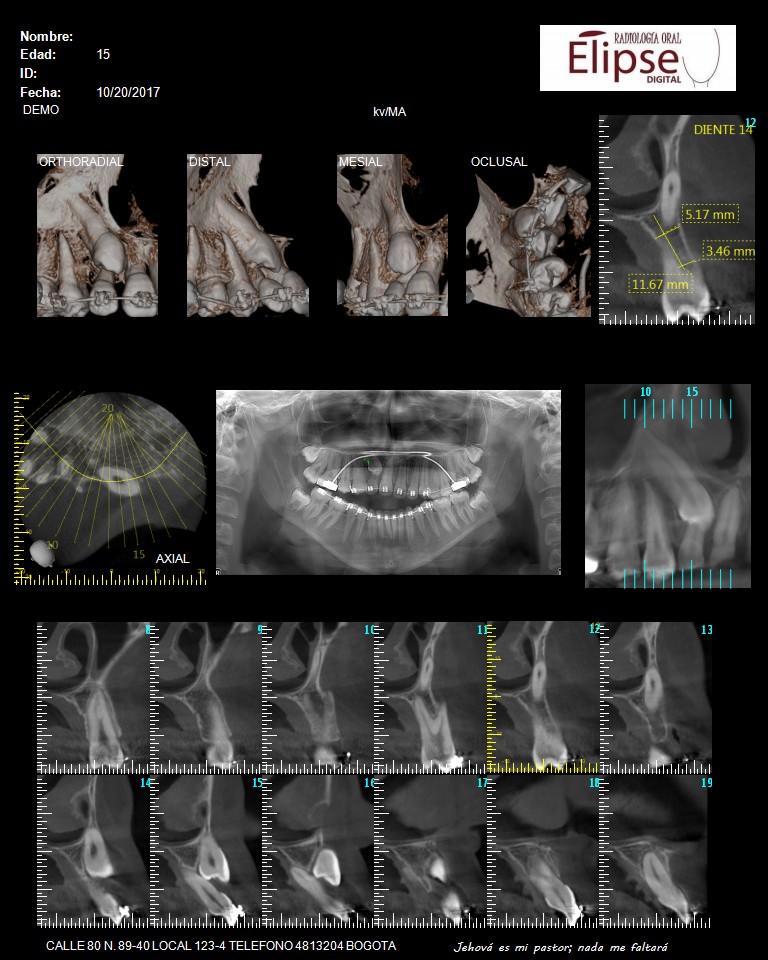

TOMOGRAFIA CONE BEAM